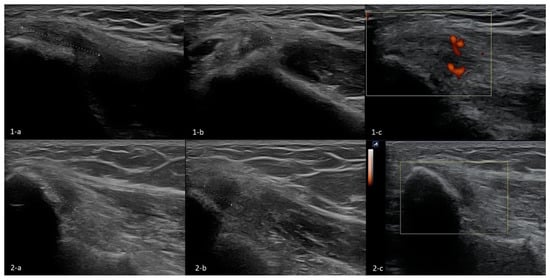

3.4.6. Ultrasonography

The Technique of Ultrasound Examination of the Medial Portion of the Elbow